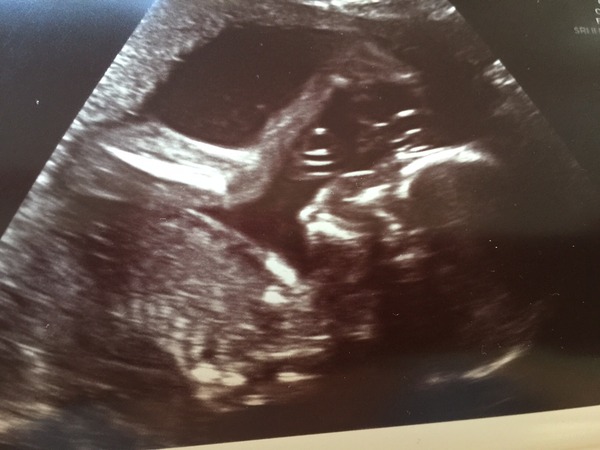

My surprise little girl Grin (two boys, was expecting no.3). Also so happy that everything was fine, only thing is a low lying placenta (again, same as last time). But at least I get one more scan, and hopefully will just move up out of way as it did last time.